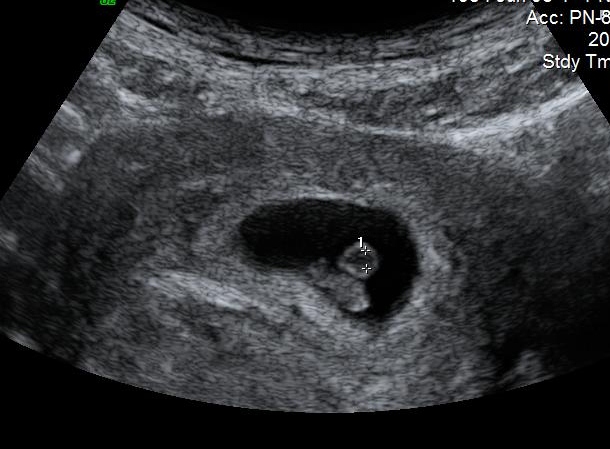

Hi everyone. I don't have a nub or potty shot, only this ultrasound pic. It is a 7 week abdominal ultrasound. Can anyone have a guess based on the Ramzi Theory??Attachment 9537